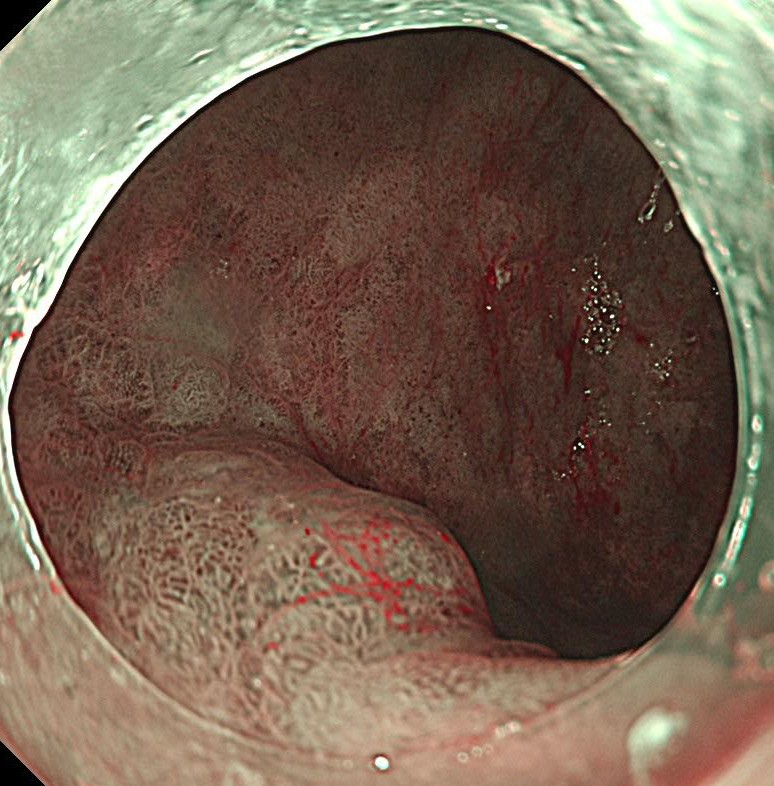

NBI(狭帯域光観察)を用いると腫瘍の不整像がはっきりわかります。